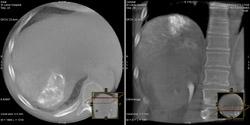

The patient had undergone a previous embolization of a large tumor located in the left lateral segment of his liver. When the patient was seen for a follow-up computed tomography (CT) scan, the CT image displayed retention of the embolic agent in approximately 85 percent of the tumor. A new nodule was also identified in the right lobe of his liver. This nodule was not present in the previous study. The patient was scheduled for a repeat embolization of the large mass and an embolization of the right hepatic nodule.

His focus then shifted to the nodule in the right lobe. Using Innova CT, a 3-D CT of the liver was performed. It clearly showed the artery that was supplying the nodule. Ringold repositioned the catheter to embolize the vessel.